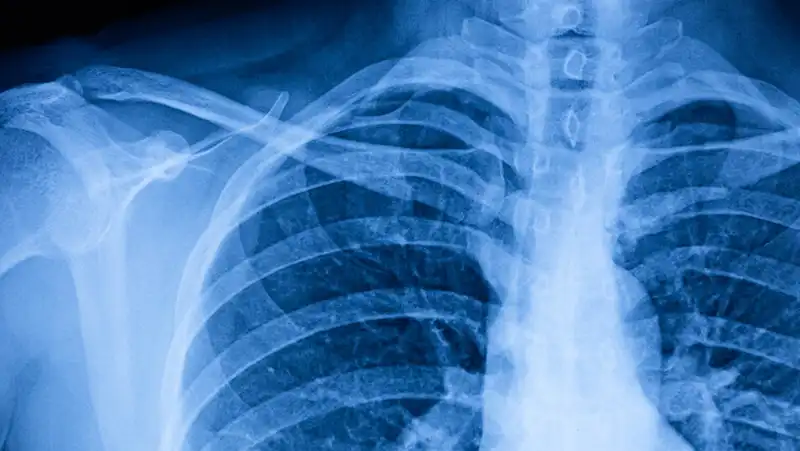

Ma ad allarmare gli esperti è anche il maggiore impatto di forme influenzali pesanti sulla popolazione più giovane. L’influenza quest’anno “sembra infatti avere una patogenicità superiore rispetto agli altri anni e stiamo osservando più ricoveri per polmonite in pazienti sani e giovani. Alcuni di questi pazienti hanno bisogno del ricovero e in alcuni casi anche del ricorso alla terapia intensiva”, spiega Marco Falcone, direttore del reparto di Malattie infettive all’Azienda ospedaliero-universitaria pisana. Le polmoniti causate dall’influenza, inoltre, “tendono a complicarsi più frequentemente con sovrainfezioni batteriche, come quelle causate da Staphylococcus aureus o Pneumococco”.

Ancora non è chiaro se queste forme particolarmente severe siano dovute a un calo dell’immunità verso i virus dell’influenza dopo due anni di pandemia o a varianti virali più aggressive. Tra le complicanze dell’influenza, poi, i medici stanno osservando anche una forma di spossatezza che si protrae per diverso tempo dopo l’infezione, simile al long-Covid. Quanto al Covid, casi si stanno verificando soprattutto in persone fragili, immunodepresse, spesso senza richiamo vaccinale.